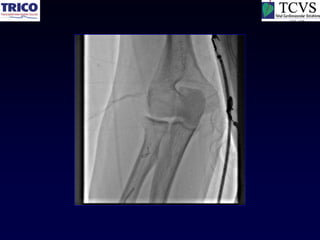

Anterior Tibial PTA

It is the limitation of hardware…